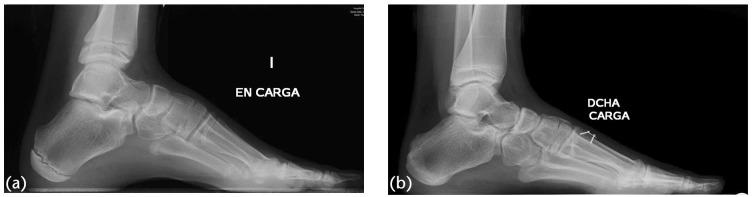

如何治疗儿童及青少年高弓足?

How to manage pes cavus in children and adolescents?

Pes cavus in its different forms is not a pathological entity, but rather the manifestation of multiple diseases.Cavovarus, a form of cavus foot, should never be considered a physiological deformity. A neurological condition should always be excluded.The evolution of pes cavovarus is unpredictable because of the large number of conditions involved in its aetiology, as well as their variable degree of expression. About 66% of cavovarus feet are the result of subtle neurological diseases, which only become evident later in life.Although surgery may not change quality of life, recent studies suggest that it may improve foot posture and reduce walking instability.The aim of treatment is to preserve a painless, plantigrade, mobile foot. Management consists of correcting bone deformity while preserving movement, and the wise use of rebalancing techniques. Arthrodesis should only be a salvage procedure. Cite this article: 2021;6:510-517. DOI: 10.1302/2058-5241.6.210021.

不同形式的高弓足并非一种病理实体,而是多种疾病的表现。高弓内翻足作为高弓足的一种形式,绝不应被视为生理性畸形。必须始终排除神经疾病。由于高弓内翻足病因涉及多种情况及其不同程度的表现,其演变不可预测。约66%的高弓内翻足是由细微的神经疾病导致的,这些疾病在生命后期才会显现出来。尽管手术可能不会改变生活质量,但最近的研究表明,手术可能会改善足部姿势并减少行走不稳。治疗的目的是保持无痛、足底着地、可活动的足部。治疗包括在保留活动能力的同时纠正骨骼畸形,并明智地运用重新平衡技术。关节融合术应仅作为一种挽救性手术。引用本文:2021;6:510 - 517。DOI: 10.1302/2058 - 5241.6.210021。